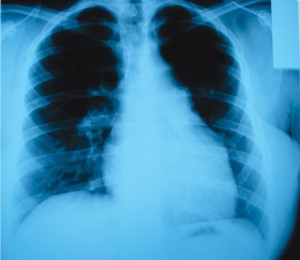

Postero-anterior and left profile chest Xray shows: right heart hypertrophy, discretely prominent middle left arch in the superior 2/3, moderate dilatation of the central pulmonary arteries, pulmonary circulation cephalization. Pleuropericardial adhesion on the left inferior arch (Figure 1A and 1B).

Figure 1A and 2B. Postero-anterior and left profile chest X-ray shows: right heart hypertrophy, discretely prominent middle left arch in the superior 2/3, moderate dilatation of the central pulmonary arteries, pulmonary circulation cephalization. Pleuropericardial adhesion on the left inferior arch.